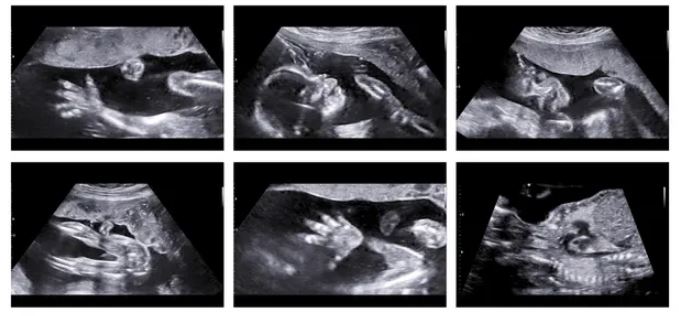

Teknologjia përdor inteligjencën artificiale për të analizuar, placentën e tyre nëpërmjet imazheve me ultratinguj të marra gjatë skanerit 12-javor të grave dhe për t’u caktuar atyre një rezultat rreziku – i ngjashëm me vlerësimin e rrezikut të tremujorit të parë për sindromën Down që ofrohet në mënyrë rutinore në këtë pikë në shtatzënitë e grave.

Placenta mund të vizualizohet duke përdorur ultratinguj, bëhet matja e saj dhe të gjitha enët e vogla të gjakut që e furnizojnë atë, por kjo kërkon shumë kohë, duke e bërë këtë jopraktike për ekzaminimin rutinë të shtatzënisë së hershme. Pra, Universiteti i Oksfordit ka përdorur mësimin e makinerive për të zhvilluar një mjet, të trajnuar në mijëra imazhe me ultratinguj ku placenta është shënuar me kujdes, për të automatizuar procesin e njohjes.

“Ajo që ne kemi arritur është një metodë plotësisht e automatizuar, e inteligjencës artificiale për të parë dhe matur placentën, kështu që befas, ne kemi një mjet kompjuterik që mund t’ju tregojë madhësinë dhe vaskularizimi i placentës në kohë reale, “tha Collins.

Një studim pilot në 143 gra tregoi se mjeti mund të dallonte foshnjat që ishin të rrezikuar nga zhvillimi i pre-eklampsisë dhe kufizimit të rritjes së fetusit.